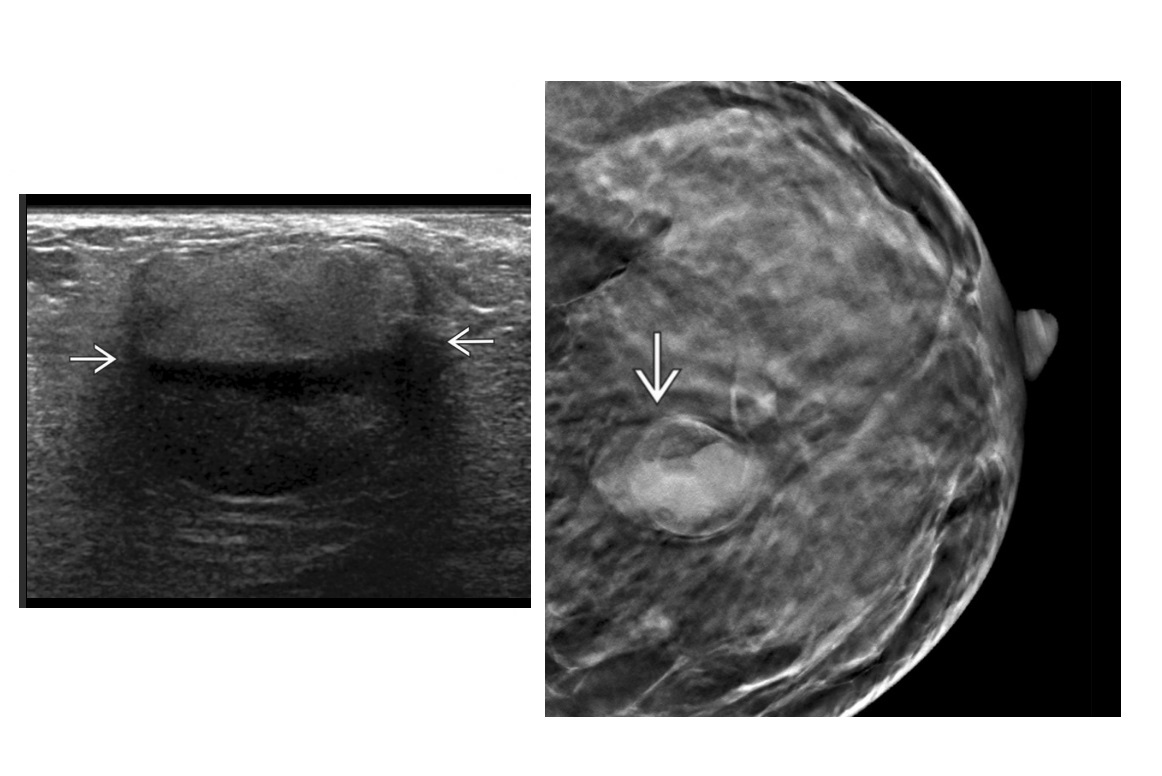

Intracapsular vs extracapsulat implant rupture. what signs?

Intracapsular

- Linguine on MRI

- Stepplader on US

Extracapsular

- Snowstrom on US

Water-suppressed STIR: Only silicone is bright

Depict extracapsular silicone, extent